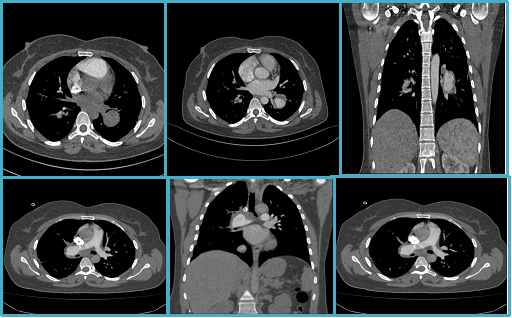

A 44-years-old female presented with complaints of recurrent hemoptysis and persistent chest pain. She had no history of significant trauma, deep vein thrombosis, coagulopathies or other predisposing vascular conditions. Her past medical history was unremarkable, and she denied recent infections or autoimmune disorders. Initial imaging was performed with a non-contrast chest CT, and an oval-shaped mass was revealed in the left hilum, raising suspicion for a vascular anomaly. Contrast-enhanced CT angiography further delineated the lesion as an aneurysm in the left interlobar pulmonary artery, measuring several millimeters in diameter. The aneurysm was compressing the adjacent segmental bronchus and was associated with thrombus formation extending into the segmental and subsegmental bronchi supplying the left lower lung lobe. Follow-up imaging (1 year later) was done: the previously noted left interlobar artery aneurysm was no longer visualized, suggesting possible spontaneous resolution or thrombosis. However, a new aneurysm was identified in the right main pulmonary artery. This new aneurysm was associated with pulmonary micro-thrombosis, raising concerns for an underlying systemic or vascular pathology predisposing to aneurysm formation. The patient was referred to rheumatologist for laboratory evaluation and systemic therapy initiation. Due to disease progression, consultation with a vascular surgeon in Vienna, Austria was arranged. However, the patient refused surgical intervention. Long-term management includes ongoing imaging surveillance and symptomatic treatment to mitigate further complications.

Figure 1a-c. The first three images depict aneurysm in the left interlobar artery Figure 1a-c: Aneurysm in the left interlobar artery (initial imaging).

Figure 2d-f. Migratory aneurysm in the right main pulmonary artery (follow-up imaging); the last 3 images are follow-up imaging.